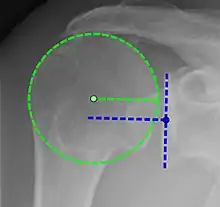

Projectional radiograph of normal glenohumeral position.[47]

X-ray projectional radiography cannot directly reveal tears of the rotator cuff, a 'soft tissue', and consequently, normal X-rays cannot exclude a damaged cuff. However, indirect evidence of pathology may be seen in instances where one or more of the tendons have undergone degenerative calcification (calcific tendinitis). The humeral head may migrate upwards (high-riding humeral head) secondary to tears of the infraspinatus, or combined tears of the supraspinatus and infraspinatus.[47] The migration can be measured by the distance between:

• A line crossing the center of a line between the superior and inferior rims of the glenoid articular surface (blue in image).

• The center of a "best-fit" circle positioned over the humeral articular surface (green in image)

Normally, the former is positioned inferiorly to the latter, and a reversal is therefore indicating a rotator cuff tear.[47] Prolonged contact between a high-riding humeral head and the acromion above it, may lead to X-rays findings of wear on the humeral head and acromion and secondary degenerative arthritis of the glenohumeral joint (the ball and socket joint of the shoulder), called cuff arthropathy, may follow.[46] Incidental X-ray findings of bone spurs at the adjacent acromioclavicular joint may show a bone spur growing from the outer edge of the clavicle downwards towards the rotator cuff. Spurs may also be seen on the underside of the acromion, once thought to cause direct fraying of the rotator cuff from contact friction, a concept currently regarded as controversial.